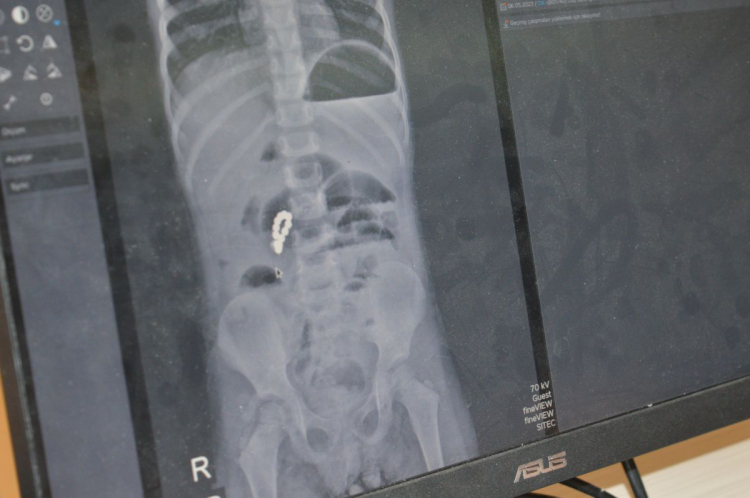

Ertesi gün öğle saatlerinde tekrar hastanenin yolunu tutan aile, bu kez çekilen röntgen filmiyle şoke oldu. Eda’nın bağırsaklarında yabancı cisimler tespit edildi. Zaman kaybetmeden Mardin Eğitim ve Araştırma Hastanesi’ne sevk edilen küçük kız, Çocuk Cerrahi Uzmanı Op. Dr. Mürsel Haspulat tarafından acil ameliyata alındı.

Ameliyathandaki tablo, durumun ciddiyetini ortaya koydu. Eda’nın farklı zamanlarda yuttuğu 8 adet güçlü mıknatıs, bağırsak içinde birbirini çekerek dokuları sıkıştırmış, bağırsakları delmiş ve düğümlenmesine neden olmuştu.

Op. Dr. Mürsel Haspulat ve ekibi, yaklaşık 3 saat süren zorlu bir operasyonla bağırsakları tek tek onardı. Ameliyatın ortasında tekrar röntgen çekilerek içeride başka bir parça kalıp kalmadığı kontrol edildi. Son parçanın da çıkarılmasıyla Eda hayata tutundu ancak vücudu büyük hasar aldığı için 6 gün boyunca yoğun bakımda yaşam mücadelesi verdi.